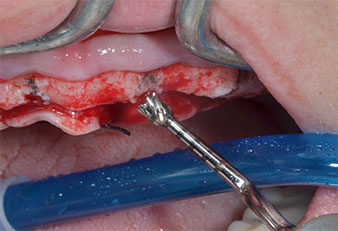

Ein flammenförmiges, diamantiertes piezochirurgisches Instrument (Piezomed I1) wurde verwendet, um die Implantatpositionen zu markieren und die Pilotpräparationen durchzuführen (Abb. 3). Dabei wurde darauf geachtet, eine Auf- und Abbewegung mit reduzierter Leistung, voller Spülung und niedrigem Druck (unter 300 g) anzuwenden. Als Nächstes wurde ein Pilotinstrument (Piezomed I2A/I2P) zur initialen Erweiterung der Implantatlager auf einen Durchmesser von 2 mm verwendet (Abb. 4), gefolgt von einem 3-mm-Instrument (Abb. 5).

Im vorliegenden Fall wurden die Instrumente Z25P und Z35P wegen des relativ weichen posterioren Knochens nicht verwendet, der problemlos mit dem I3A/I3P bearbeitet werden konnte.

Wegen des relativ harten Knochens (D2) an den Positionen 11 und 21 wurden die 10 mm langen Implantatlager in diesem Bereich abschließend mit einem 4-mm-Spiralbohrer, dem chirurgischen Winkelstück WS-75 L von W&H und dem W&H Implantmed Implantologiemotor in Verbindung mit dem optionalen W&H Osstell ISQ module präpariert. Im Gegensatz dazu wurde der weiche Knochen der Implantatlager im Seitenzahnbereich mit dem Piezomed I3P auf den abschließenden Durchmesser von 3 mm erweitert. Die Implantate wurden dann transgingival eingesetzt, die Einheildauer betrug drei Monate (Abb. 6-10). Die vorhandene Prothese wurde auf vier provisorischen Implantaten abgestützt (Abb. 8).